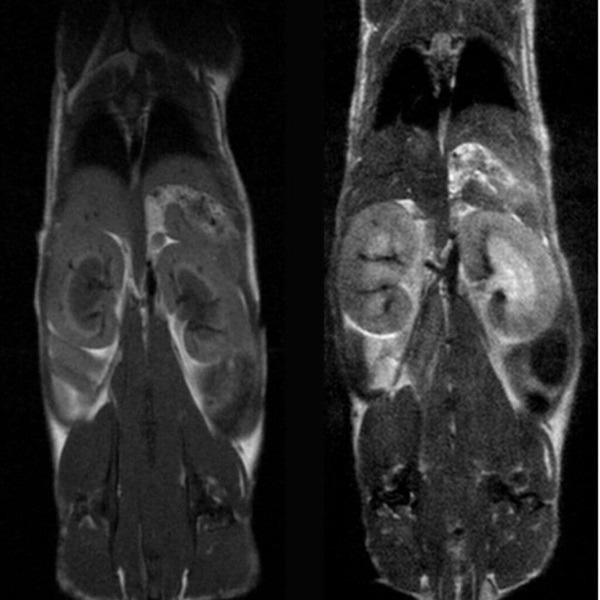

Tumor visualization in various cancer models: Fat-suppressed T2-weighted imaging can be used to detect and quantitatively characterize the growth of a wide range of cancer models. Image Credit: Scintica Instrumentation Inc

Hindlimb tumor growth: Monitoring the growth of xenograft tumor grown in the mouse hindlimb is identified with T2-weighted images. Segmentation of tumor region of interests (in red) on each tumor-containing slice allows accurate volume quantification. Image Credit: Scintica Instrumentation Inc

Cancer/oncology

The M-Series devices are suitable for studying various tumor types and disease phases. Since no alteration of tumor cells is necessary, models such as xenografts, orthotopic, transgenic, and patient-derived xenografts can be studied in a wide range of imaging subjects to focus on.

- Quantitative monitoring of tumor development

- Quantitative response evaluation for drug studies

- Tumor phenotyping, including necrosis detection

Fat-suppressed T2-weighted imaging can be used to detect and quantitatively characterize the growth of a wide range of cancer models. Image Credit: Scintica Instrumentation Inc

Monitoring the growth of xenograft tumor grown in the mouse hindlimb is identified with T2-weighted images. Segmentation of tumor region of interests (in red) on each tumor-containing slice allows accurate volume quantification. Image Credit: Scintica Instrumentation Inc